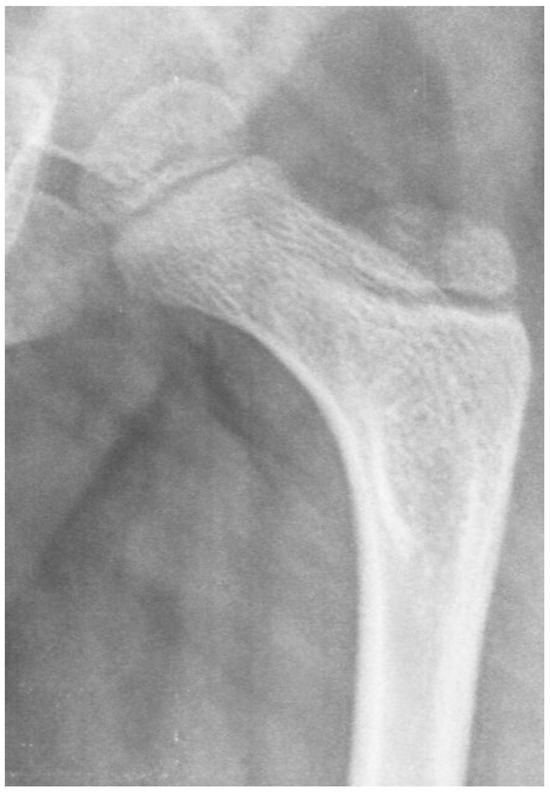

3.3.3. Pathology of Hip Development in Children with Low Tone and Muscle Weakness

3.4. Femoral Factors Influencing Hip Pathology

4.1.2. Pathologic Role of Coxa Valga and the Impact of its Correction in Weak and Hypotonic Hips

4.1.3. Pathologic Role of Coxa Valga and Treatment Options in Paralytic Hips